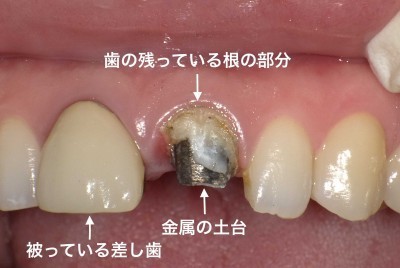

クラウン 差し歯 被せ物 を入れる前に知っておきたいポイント 渋谷

さし歯 冠 ブリッジ 歯とお口のことなら何でもわかる テーマパーク8020

さし歯 冠 ブリッジ 歯とお口のことなら何でもわかる テーマパーク8020